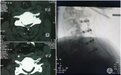

患者华XX(化名),突发颈部以下感觉麻木,不能正常行走,双手不能活动。经检查发现患者后纵韧带骨化严重,椎管内骨化占位已达到近80%,脊髓已经压迫到了“细片”状程度,严重威胁脊髓神经功能,随时有发生高位截瘫的可能。得知我院骨三科脊柱外科团队在高难度颈椎手术方面具有丰富诊疗经验,由外院转至西安交大二附院骨三科。

骨三科主任张纯教授团队仔细分析患者临床资料,考虑到患者年轻、压迫极其危险等特点,需要手术治疗,但是面临患者脊髓压迫已到临界点,随时存在瘫痪可能,手术风险极大。全面评估后,决定先行后路脊柱单开门减压手术方式,二期颈椎前路椎体次全切除减压植骨融合内固定手术。